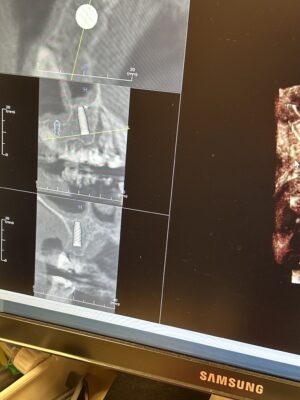

Hello,

I ran into an issue with my 81 year old Pt and thought if anyone has some insights.

This is my first implant restoration after graduation.

The implants were planned by another GP and placed by a periodontist.

#12 RC 4.1,#11 4.1 RC ,#10 3.3 NC. Straumann bone level. The periodontist placed them 6 months ago and said it is ready for…